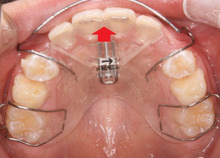

まだ骨は軟らかい、小学生なので、

骨を広げる装置を入れます。

この装置は拡大床(かくだいしょう)

といいます。